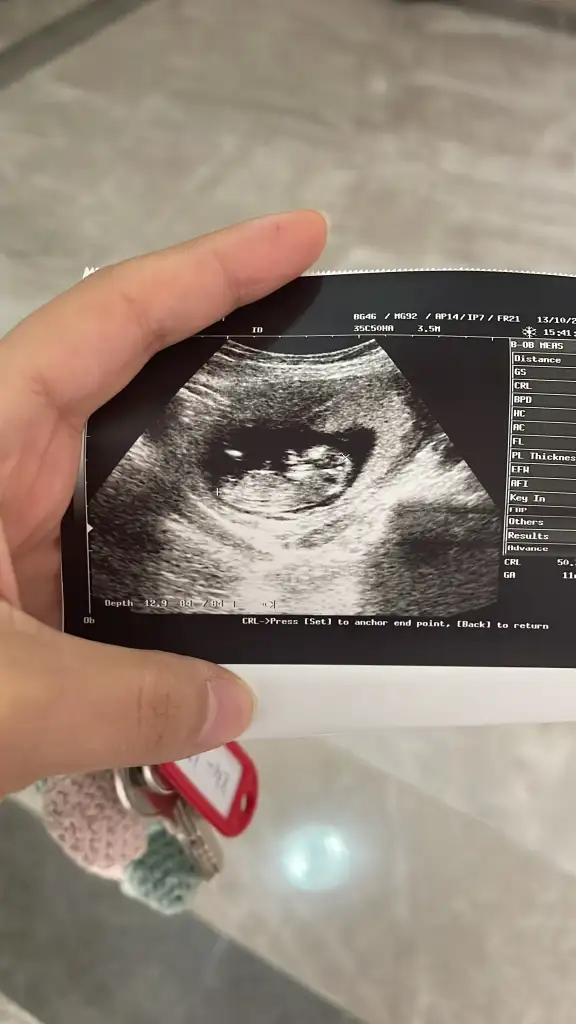

Cinsiyet tahmini

Sizi heveslendirmek istemem hiç oğlum olmadı ama sanki erkek gibi duruyor bacak arasida rabbim gönlünüzdekini hayırlı eyleyip nasıl etsin inşaallah 💜